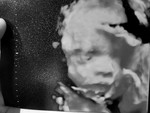

Baka may alam po kayo na open for ultrasound around pasay? Close po kasi clinic ng Doc ko. 38 weeks na po ako and d pa po na uultrasound ulit. Just to make sure lang po sana if naka pwesto na ng maayos si baby bago manganak. Ayoko ma CS.